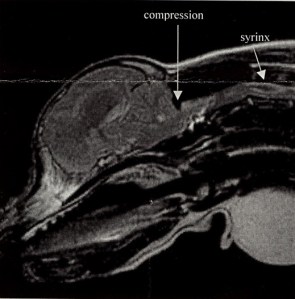

At first our local vet thought it was a muscle strain and prescribed muscle relaxants but that didn’t help. I was desperate for answers and started searching online. My main source of data was a Yahoo group for what seemed to be a Chiari-like malformation in Cavaliers and the emerging research of Claire Rusbridge in England. No one was exactly sure of the cause at that time but it was becoming clear that fluid filled cavities in the spinal cord near the brain seen via MRI were causing extreme pain in some Cavaliers. Caudal Occipital Malformation (COMS) where there is malformation at the back of the skull was also theorized to play a role as was the relatively large size of the cerebellum (back part of the brain) in many Cavaliers that seemed to cause the brain to squeeze out the bottom of the skull and obstruct the flow of spinal fluid.

I took everything I found to our vet at the time Valerie French and she referred us right away to Veterinary Neurologist Sean Sanders. Luckily he had just come back from a conference in New York where Syringohydromyelia was discussed and he saw Maya’s symptoms right. An MRI confirmed the diagnosis and she had decompression surgery in June 2003 to remove the suboccipital bone and allow the spinal fluid to move freely. Conservative treatment through Prednisone alone was considered not likely to be successful long term and the recommendation was that early surgery was more successful than waiting.